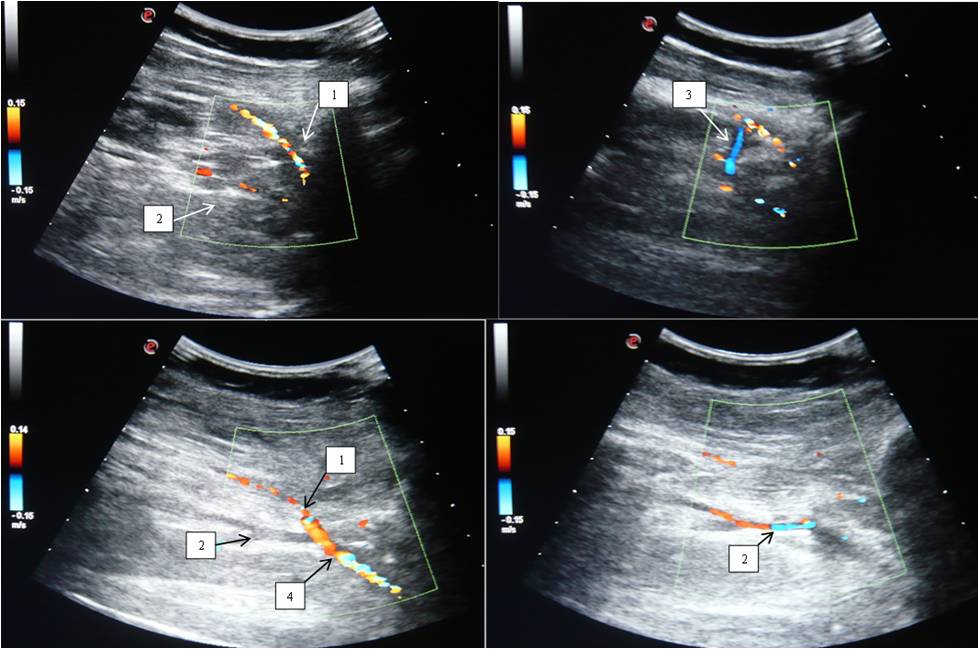

On duplex scans, PA was always represented by one trunk, in 4 patients (1.9%), high bifurcation of PA was found at the level of the proximal part of the popliteal fossa — 2 cm above the knee joint cleft. It is important to note that ATA runs in the initial parts isolated from the anterior tibial veins at an angle approximate to 60° relative to the course of PA (while the ATV runs at an angle approximate to 90°), and connects to the ATV only in the anterior intermuscular bed of the leg (Figure 3).

Fig. 3. Duplex scan of a patient with a high division of the popliteal artery.

Notes: (1) Anterior tibial artery; (2) Posterior tibial artery; (3) Anterior tibial veins; (4) Popliteal artery.

By DS data, the incidence of high bifurcation of the PA was comparable with the data of angiographic studies, but it was fewer than in the work of A. J. Tindall, et al. [15]. It is necessary to emphasize once again that the popliteal fossa region is complex in terms of vascular topography, and the sural arteries, located right in this region, could be mistaken for high bifurcation of the PA. However, the sural arteries always originated from the posterior surface of the PA, while with a high bifurcation of the PA, the ATA originated from the lateral or posterior surface of the artery. Another important practical point may be the fact of the PA deviation towards the lateral side in the distal part of the popliteal fossa, therefore the ultrasound sensor should be positioned slightly outwards the midline at the level of the distal part of the popliteal fossa. Besides, identification of variant anatomy of the PA is facilitated by positioning the ultrasound sensor lateral to the head of fibula (Figure 3).